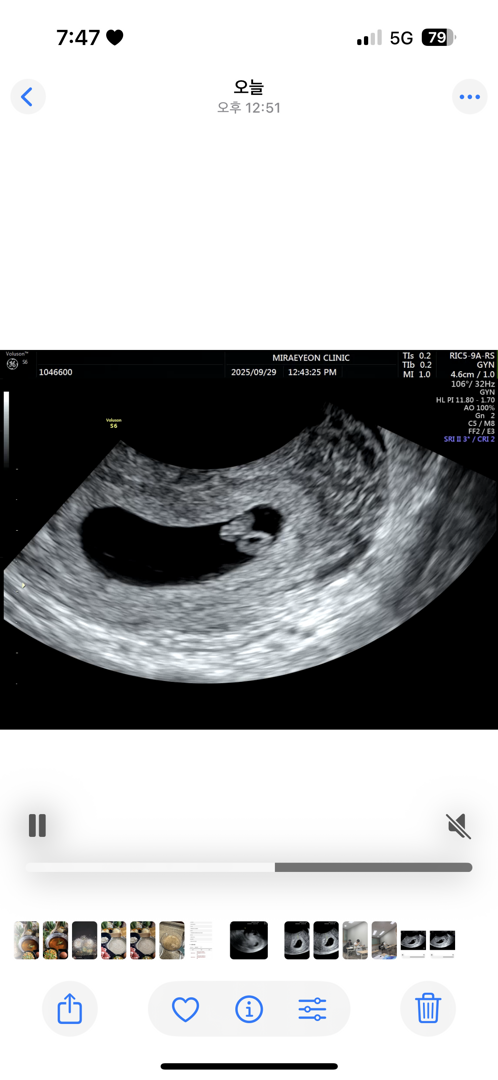

6주차 4일입니다

난황 위치보는법을 모르겠어요 입덧은 없고 먹덧이 심해요 고기 매운음긱 위주로 땡기고 과일은 그닥 안땡기네요 땡겨봤자 오렌지?? 아들일까요 딸일까요?